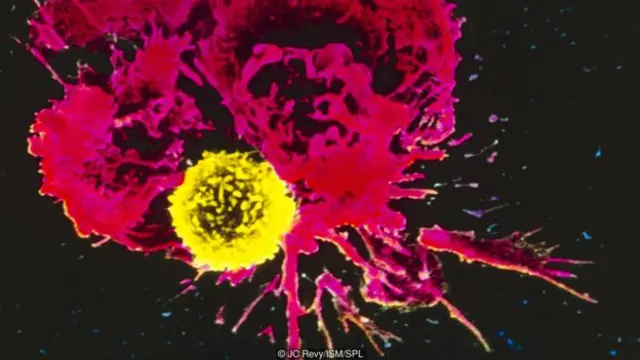

Kanser de hücre bölünmesi ile ilgilidir; ama bir farkla: Kanserli hücre, diğer hücrelerin tabi olduğu kontrollü bölünme kurallarını çiğner.

“Bu hücreler sanki farklı bir organizma gibidir” diyor Cambridge Üniversitesi’nden Timothy Weil. “Ne kadar hızlı bölünürse diğer hücrelerden daha fazla besin alabilecek ve tutunup büyüyebilecektir.”

“Yetişkin hücreler sürekli kontrol altındadır. Ama kanser bu hücrelerde kontrolün kaybolması demektir” diyor Weil.

Kanser hücrelerinin hepsi birbirinden farklıdır. Bölündüklerinde mutasyona uğrayıp değişirler. Yani kanser tümöründeki hücreler genetik olarak birbirinden farklıdır. Tıpkı diğer canlıların da zamanla genetik varyasyonlar geliştirdiği gibi.

Bütün canlılarda olduğu gibi doğal seleksiyon yoluyla en güçlünün hayatta kalması süreci işlediğinden tümördeki hücreler de daha kanserli olacak şekilde evrilir.